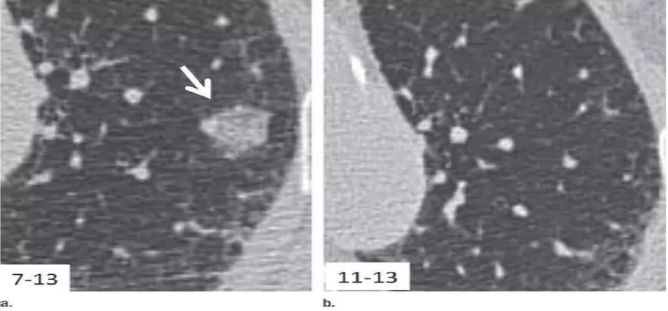

在中国人的印象里 心和肺一直是“形影不离”的 海尔兄弟 成语里有 撕心裂肺 狼心狗肺 没心没肺 …… 医学术语里有 心肺功能 心肺复苏 心肺康复 …… 尤其是当肺部查出“小阴影” 心更是脱不了关系 每天都惴惴不安 今天肿医君就来带大家看看 这让人烦恼的 肺部结节 Part.1: 肺部结节 真实病例: 张阿姨今年48岁,单位体检结果显示,肺上有一个0.8cm的小结节。张阿姨听说肺结节会变成肺癌,她担心极了,让儿子帮忙上网查询,向其他人咨询,可她得到的建议多种多样,让刘阿姨无所适从。 慢慢长大会不会变成肺癌啊 肺癌是世界上发病率及死亡率最高的恶性肿瘤,也是我国发病率和死亡率最高的疾病。目前约 75% 的肺癌患者在诊断时已属晚期,5年生存率仅为 15.6%。提高肺癌生存率的唯一途径是端口前移,早发现、早诊断和早治疗。 美国《化学文摘》2018全球癌症统计报告显示 肺癌(蓝色)高居发病率和死亡率之首 全球发病率11.6% 全球死亡率18.4% 湖南省肿瘤医院胸外一科 主任医师 陈跃军 很多患者忧心忡忡,不知道是否该进行进一步检查。如果对体检报告中的一些疾病迹象置若罔闻,等“小结节”长大变成了“肿块”,往往已错过最佳手术时机。那么我们应该怎么正确对待肺部结节呢? Part.2: 结节的分类 知识点 肺部结节(solitary pulmonary nodule,简称SPN)是肺实质完全包围的单发小病灶,类圆形或不规则形状,通常边界清晰,由肺实质包裹,不累及肺门和胸腔纵隔胸膜,不引发肺炎、肺不张或胸腔积液的组织。 肺结节分类如下 按大小: 肺结节中,直径1cm以内的称为小结节,直径0.5cm以内为微结节。局部病灶直径>3cm者称为肺肿块,也有医院将其报告为肺肿物或肺占位。 肺部结节尺寸越大,肺癌的可能性相对较大。 按数量: 肺结节可以是孤立性或多发性,孤立性肺结节即单个病灶,多无明显症状,属于边界清楚、密度增高且周围被含气肺组织包绕的软组织影。2个及以上病灶称为多发性肺结节。 肺结节的个数与肺癌可能性没有相关性 按密度: 根据病灶密度不同,肺结节还可分为实性肺结节和亚实性(非实性)肺结节,后者包括纯磨玻璃样结节。实性肺结节是肺内局限的密度增高影,病变密度相对较高,掩盖其中走行的肺细小支气管影和血管影(肺纹理);纯磨玻璃结节指CT显示的肺内密度稍增高影,通过病灶仍然能看到肺纹理影,就像透过磨玻璃观察到相对模糊的影像一样。 磨玻璃样结节尤其是持续存在的磨玻璃样结节,一般是肿瘤性病变 湖南省肿瘤医院胸外一科 主任医师 陈跃军 发现肺结节之后,不用过分紧张,但也不能掉以轻心,大部分肺结节都是良性的,只有少数肺结节是恶性的。 Part.3: 区分结节性质 结节良性的三大表现 1、 结构清晰,边缘平滑。内含脂肪和钙化的实性结节(箭头),符合错构瘤表现。建议进一步 CT 随访。 源自美国Fleischner 学会2017 年公布案例图(下同) 2、 有明显钙化痕迹。CT 图像显示边界清楚的中心钙化(a)或层状钙化(b)结节,均为典型的肉芽肿表现。建议进一步 CT 随访。 3、没有变大的趋势,甚至逐渐消失。(a)左肺上叶层厚 1 mm 的 CT 横断面图像,显示一个模糊的 10 mm 大小磨玻璃样结节(箭头)。(b)4 个月后的 CT 随访图像,显示未经治疗的病变在随访间期消失,符合良性病因,如局灶性感染。 结节恶性的三大表现 1、 毛刺状结节 左肺上叶层厚 1 mm 的 CT 横断面图像,显示一个可疑的实性毛刺状结节(箭头)。手术证实为浸润性腺癌。 2、 磨玻璃区域逐渐长大的结节 (a)右肺中部层厚 1 mm 的 CT 横断面图像,显示一个 10 mm 大小的纯磨玻璃样结节(箭头)。(b)同一位置 15 个月后的 CT 随访图像,显示病变的不透明度只有很小增加。(c)取得 b 图 10 个月后,同一位置的 CT 图像,显示结节已发展成较大的实性结节。手术切除证实为 1A 期浸润性鳞屑样为主的腺癌 3、实性结节逐渐变大的结节 (a)右肺下叶上段层厚 1 mm 的 CT 横断面图像,显示一个高度可疑(较大、磨玻璃样外观和实性形态)的部分实性结节(箭头)。(b)3 个月后的 CT 随访图像显示,实性成分的大小逐渐增加。手术显示为浸润性腺癌。 除了上述影像资料,咨询者的生活方式也是判断依据。 肺癌的高危人群 (1)年龄在55岁以上; (2)年数乘以每天吸烟的支数>400支*年的吸烟患者,其中也包括曾经吸烟,但戒烟时间不足15年者;被动吸烟者; (3)有职业暴露史(石棉、铍、铀、氡等接触者); (4)有恶性肿瘤病史或肺癌家族史; (5)有慢性阻塞性肺疾病(COPD)或弥漫性肺纤维化病史。 Part.4: 发现结节怎么做? 1、肺部小结节并不等于肺癌,并且大部分是良性的,有的通过保守治疗如抗炎或抗痨治疗,甚至不做任何治疗观察后消失。因为人体有自身免疫力的,只要营养好,一般的炎性病变可自行吸收。 2、当医生判断结节恶性可能性较小时,还是建议患者要定期检查胸部CT。5毫米以下的微结节每年复查一次,5至10毫米的小结节每三个月复查一次,随访三至五年。 CT在肺内病变中的诊断优势非常明显,CT通过显示组织横断面及三维结构图像进行诊查,有效避免了肺与心脏、纵隔、横膈等组织的重叠,能发现肺尖、脊柱旁、靠近胸膜、心脏后方等部位胸片难以发现的病灶。另外,低剂量CT筛查所产生的射线剂量很低,对人体的影响极低。 3、当医生判断为恶性可能性较大时,应早期进行手术(胸腔镜)治疗。国内外多个研究结果显示,经过手术治疗的I期患者的10年生存率达到了90%以上。 目前微创胸腔镜手术是治疗肺部小结节、早期肺癌的主要方法。胸腔镜手术应用广泛,只需一个1cm胸腔镜观察孔和一个2-3cm操作孔,行肺叶或肺段切除术,疗效明确,创伤非常小,疼痛轻,术后恢复快,不需要做任何的化疗和放疗。 在我们临床工作中对上千例磨玻璃结节、微小结节患者的长期临床观察研究结果显示,90%以上患者的结节没有发生变化,10%的患者在随访过程中发现结节长大或实质成分增加等改变,及时手术,但没有一例出现复发转移,所以只要找对了专家,定期随访,并不会耽误治疗。 最危险的情况其实是病人发现肺部结节去看医生,医生考虑肺部小结节可暂时不处理,建议定期复查,而病人把不手术、不服药误认为没病,一直拖到出现症状后再去就诊,耽误了病情。